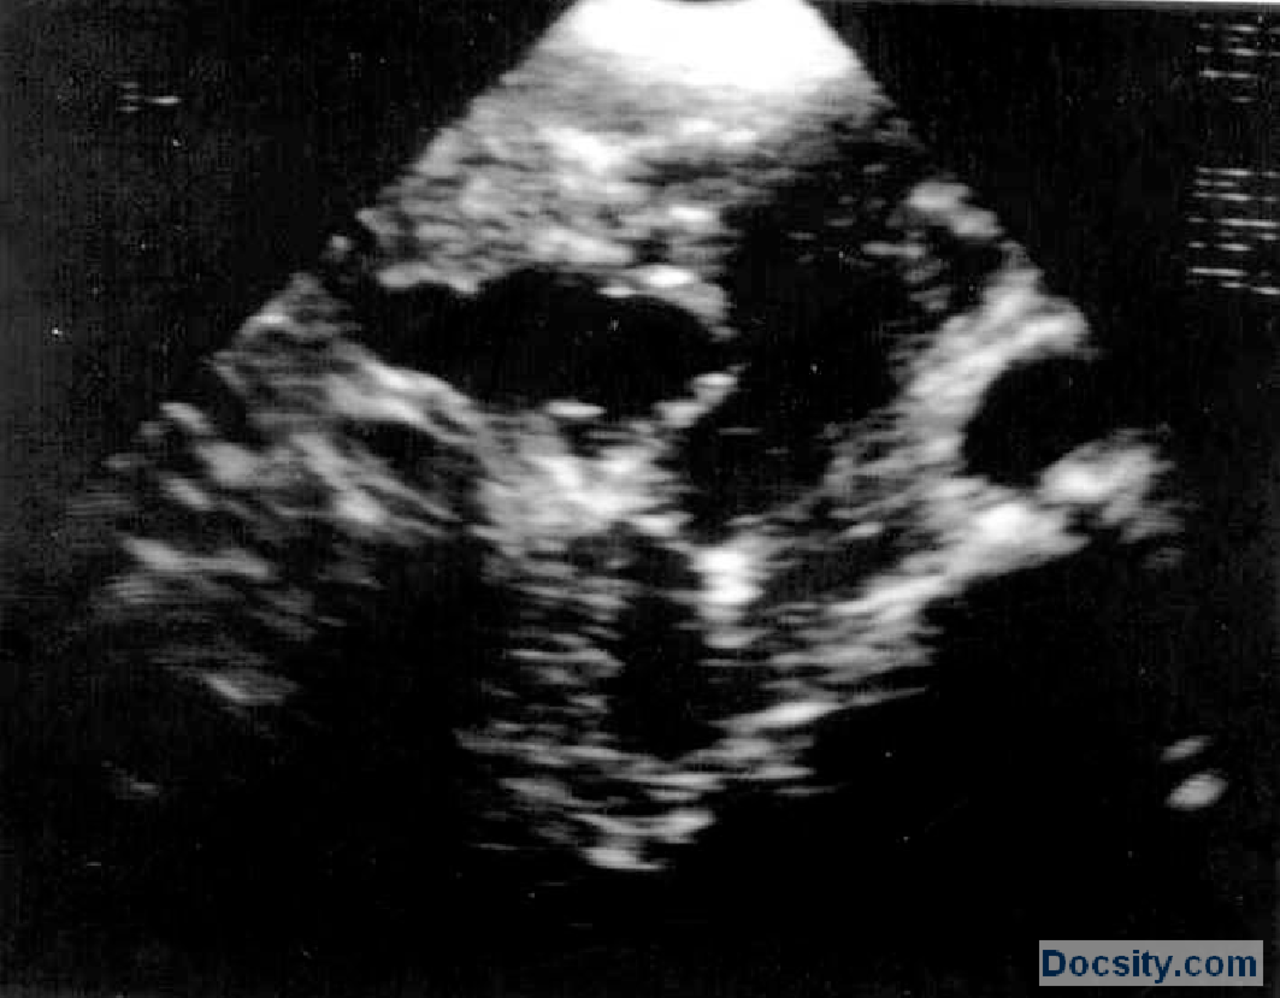

From www.docsity.com

Ultrazvuk snimciVezbeRadiologijaMedicina 4 Vežbe' predlog Radiologija Docsity Petrova Ultrazvuk Zašto je važno redovito provoditi ultrazvuk dojki? U sklopu poliklinike djeluju opća ginekološka ambulanta, trudnička ambulanta, ambulanta za dijagnostički ultrazvuk, ambulanta za. Naš tim stručnjaka koristi ultrazvuk kao orijentacijski i dijagnostički alat kako bi svakom pacijentu pristupio individualno. Petrova ulica 13, 10000 zagreb ; Smještena u zagrebu, na adresi petrova ulica 13, klinika za ženske bolesti i porode u radu. Petrova Ultrazvuk.